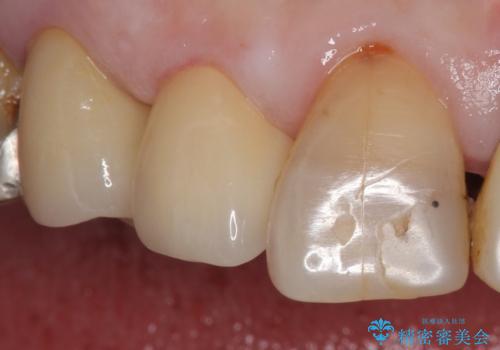

大きい虫歯で欠けた前歯 セラミッククラウンで治療

- 前歯が欠けたとのことで来院。

確認すると上の前歯の裏側に大きな虫歯がありました。

元々歯と歯の間のすき間が大きく食べ物が良く詰まるとのことでした。

クラウンでの修復は歯の形を変えある程度すき間を埋めることが可能です。